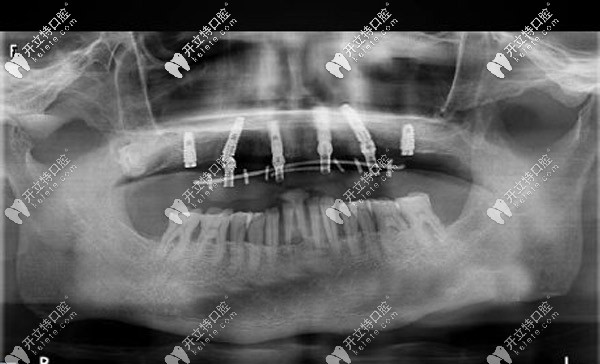

與周老先生進(jìn)行溝通后,確定了種植體嵌入位置、數(shù)量、種植深度、植體傾斜角度等等,并采用上頜6顆即刻種植技術(shù),運(yùn)用“數(shù)字化動(dòng)態(tài)導(dǎo)航種植”方案。

口腔種植中的動(dòng)態(tài)導(dǎo)航就像汽車導(dǎo)航一樣,在顧客進(jìn)行種植牙手術(shù)時(shí),可根據(jù)提前設(shè)計(jì)好的種植方案,通過(guò)顯示屏實(shí)時(shí)直觀地看到種植體植入頜骨的全過(guò)程。

全程監(jiān)控種植位點(diǎn)、角度、深度,能夠避免損傷重要的解剖結(jié)構(gòu)。這樣做可以節(jié)省大量的種植時(shí)間,縮短牙骨暴露在外的時(shí)間,保存了牙骨的活性,有利于植體和牙槽骨的緊密結(jié)合。